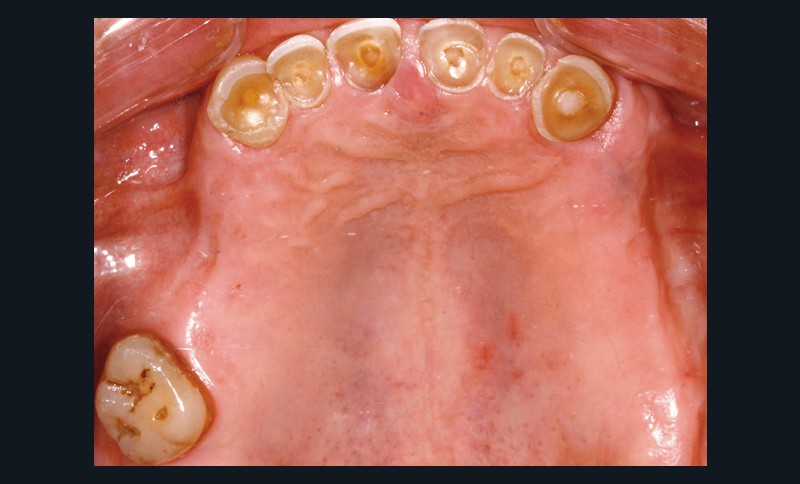

Un patient de 68 ans arrive au cabinet ; il présente de nombreux édentements ainsi qu’une usure parafonctionnelle très avancée.

Examen clinique (fig. 1-6)

• L’examen intrabuccal montre de nombreux édentements non compensés (14, 15, 16, 24, 25, 26, 27, 47 et 36) ainsi que des pertes de substance très importantes, notamment dans le secteur antérieur.

• Le bilan esthétique nous indique plusieurs points disgracieux :

– dysharmonie des contours gingivaux (ligne des collets) avec une ligne du sourire basse [1] ;

– perte de substance extrême du bloc incisivo-canin maxillaire et des incisives mandibulaires ;

– visibilité très limitée des dents lors d’un sourire forcé ;

– égressions compensatoires.